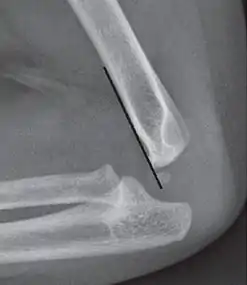

The anterior humeral line is not reliable in children with sparse ossification of the capitulum, such as in this 6 months old child.[9]